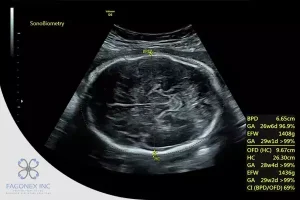

BPD measures the width of the fetal head, while OFD measures the length. When combined, these values help determine the cephalic index (CI):

CI = (BPD / OFD) × 100

- Normal CI: 74–83%

- High CI (>85%) suggests brachycephaly (short skull)

- Low CI (<70%) suggests dolichocephaly (long, narrow skull)

Use of Sono Mobile™️ CT61 in Biometry

The Sono Mobile™️ CT61 is a next-generation portable ultrasound system designed for high-performance point-of-care imaging. It offers clinicians fast and accurate access to fetal biometric measurements, including BPD, FL, and AC. Engineered for both precision and convenience, this device features a dual-probe design; combining both convex and endovaginal probes in a single unit. With the push of a button, users can seamlessly switch between modes, dramatically increasing the mobility, efficiency, and clinical readiness of the system in diverse obstetric settings.

Its high-resolution imaging, lightweight ergonomic design, and intuitive touchscreen interface make the Sono Mobile™️ CT61 ideal for obstetricians, gynecologists, radiologists, and sonographers working in hospitals, women’s health clinics, fertility centers, and even mobile ultrasound services. Preloaded fetal biometry presets and caliper guidance reduce manual steps and minimize user error, making it a powerful solution for both routine prenatal care and advanced fetal assessments.